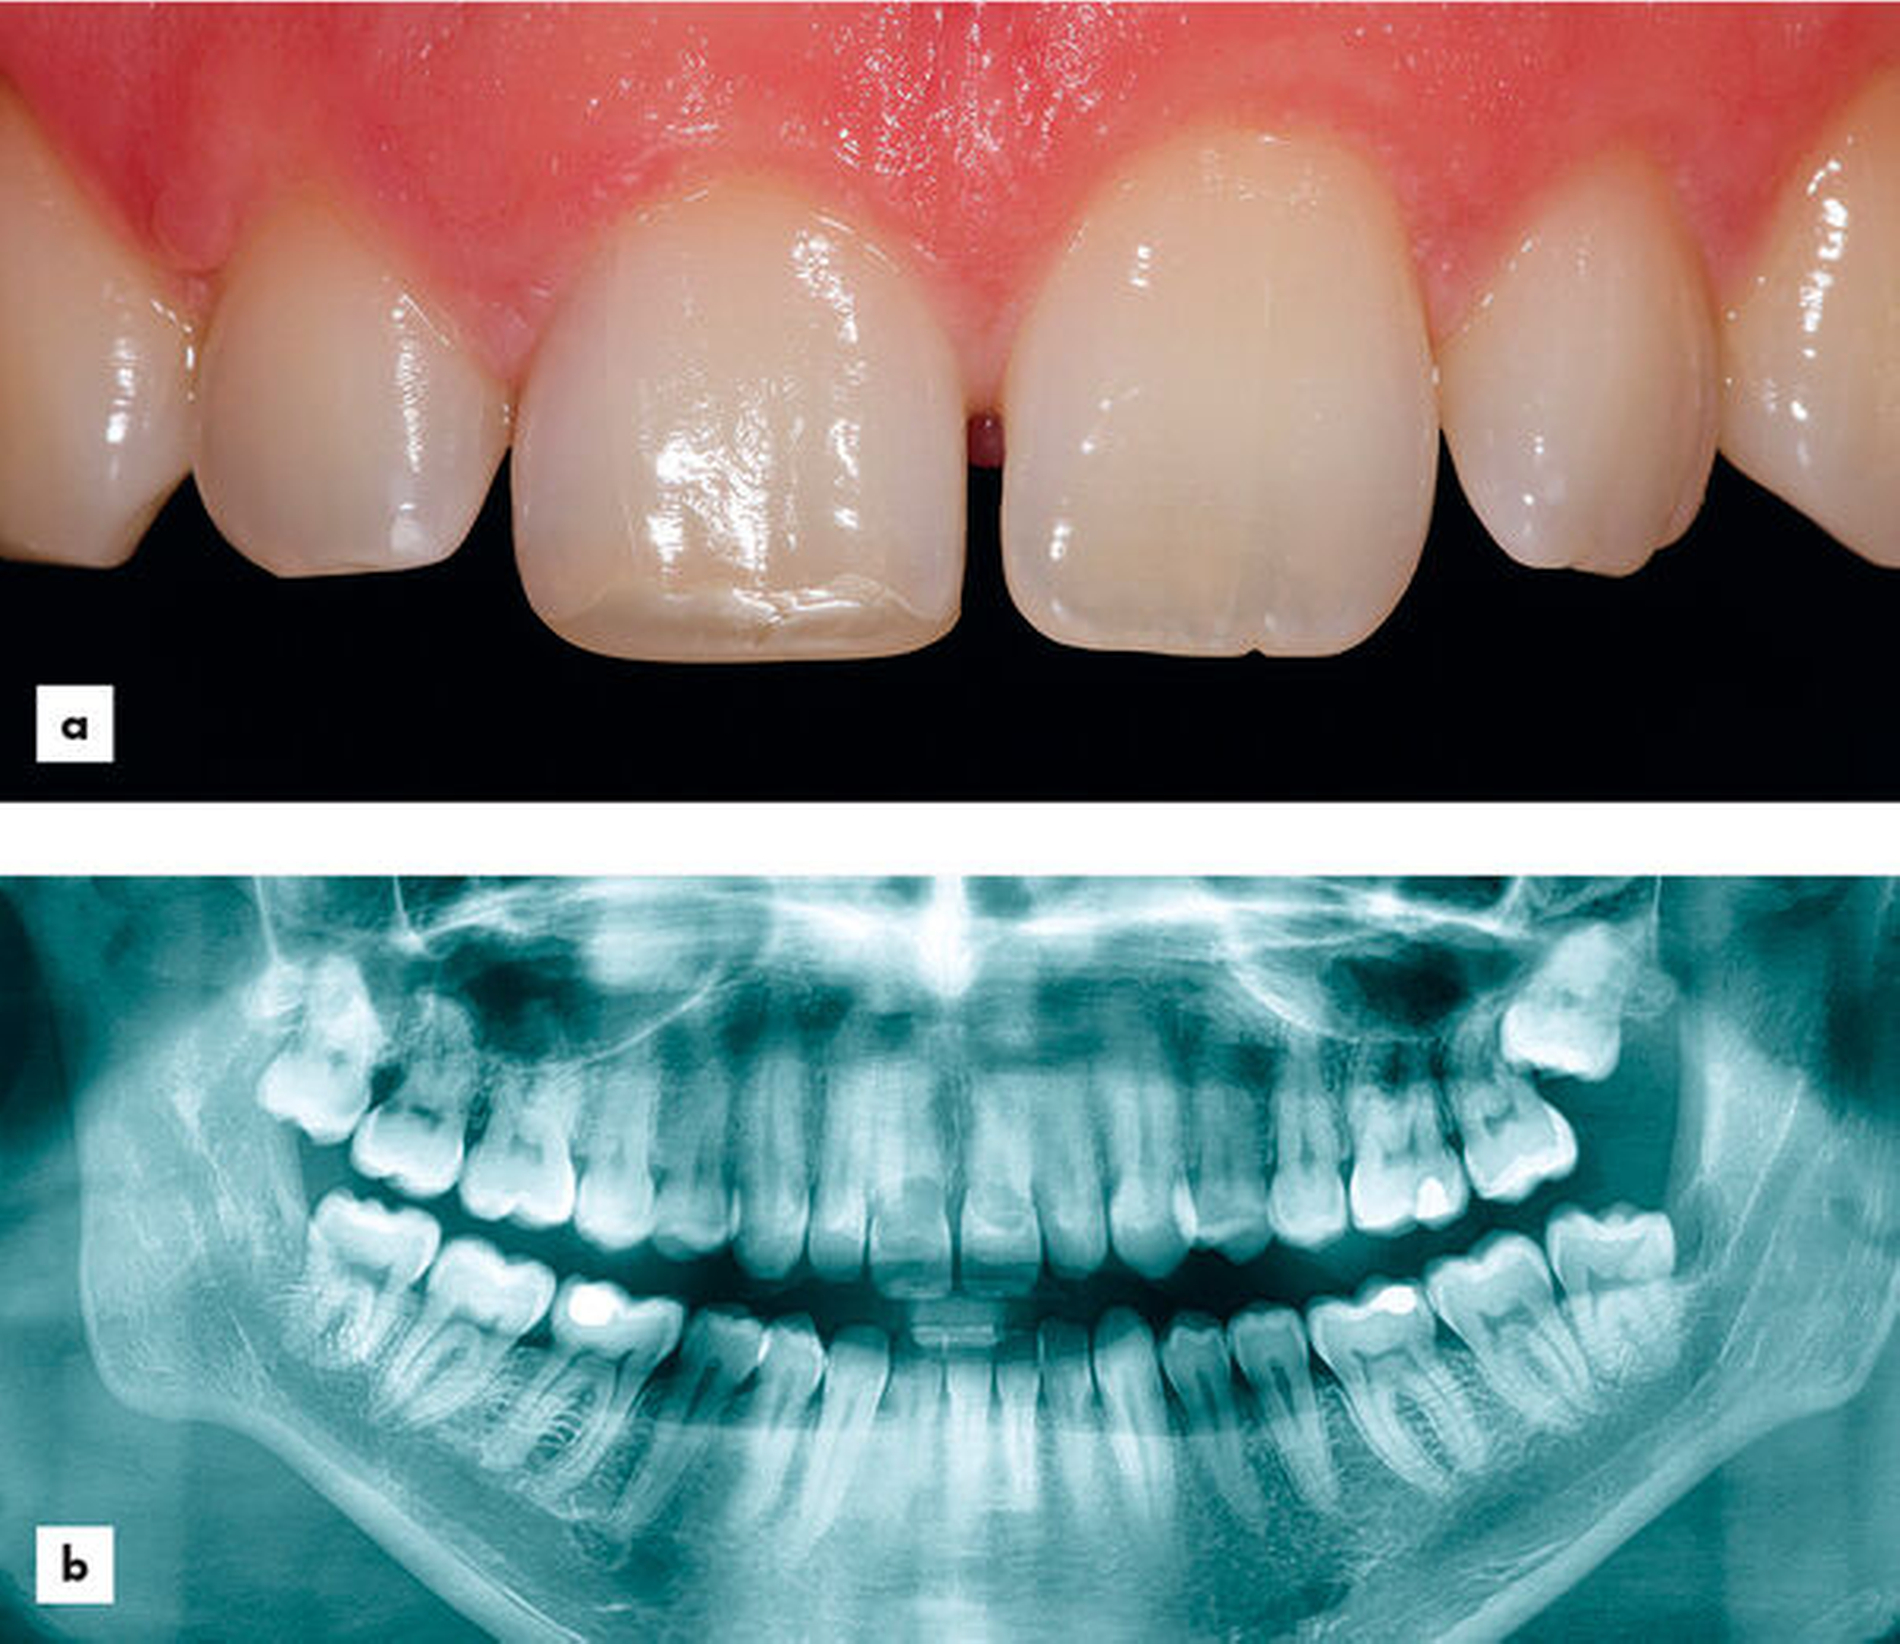

Der allgemeinzahnmedizinische Befund zeigte erhöhte Sondierungstiefen palatinal an den Zähnen 11 und 21 mit starker Blutung. Der CO2-Sensibilitätstest der Zähne 11 und 21 war verzögert, jedoch positiv. Die restlichen Zähne im Ober- und Unterkiefer zeigten keine Auffälligkeiten (Abbildung 1a).

Das OPG (Abbildung 1b) zeigte koronale Aufhellungen an Zahn 11 und 21 auf. Der Zahn 28 war retiniert und verlagert. Im DVT wurde eine deutliche Resorption der Zähne 11 und 21 ersichtlich (Abbildungen 2a, b).